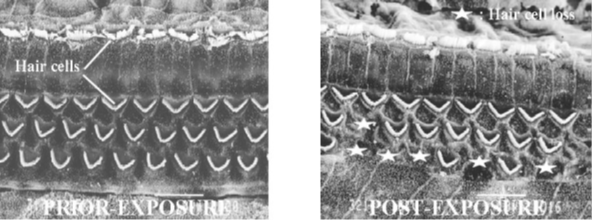

Sensorineural hearing loss is a permanent condition that usually cannot be treated medically or surgically and is associated with irreversible damage to the inner ear. The normal aging process and excessive noise exposure are both notable causes of sensorineural hearing loss. Studies show that exposure to noise damages the sensory hair cells that line the cochlea. Even moderate noise can cause twisting and swelling of hair cells and biochemical changes that reduce the hair cell sensitivity to mechanical motion, resulting in auditory fatigue. As the severity of the noise exposure increases, hair cells and supporting cells disintegrate and the associated nerve fibers eventually disappear. Occupational noise exposure is a significant cause of sensorineural hearing loss, which appears on sequential audiograms as declining sensitivity to sound, typically first at high frequencies (above 2,000 Hz), and then lower frequencies as damage continues. Often the audiogram of a person with sensorineural hearing loss will show a "Notch" at 4,000 Hz. This is a dip in the person's hearing level at 4,000 Hz and is an early indicator of sensorineural hearing loss. Results are the same for hearing tests of the ear and bone conduction testing. Sensorineural hearing loss can also result from other causes, such as viruses (e.g., mumps), congenital defects, and some medications.